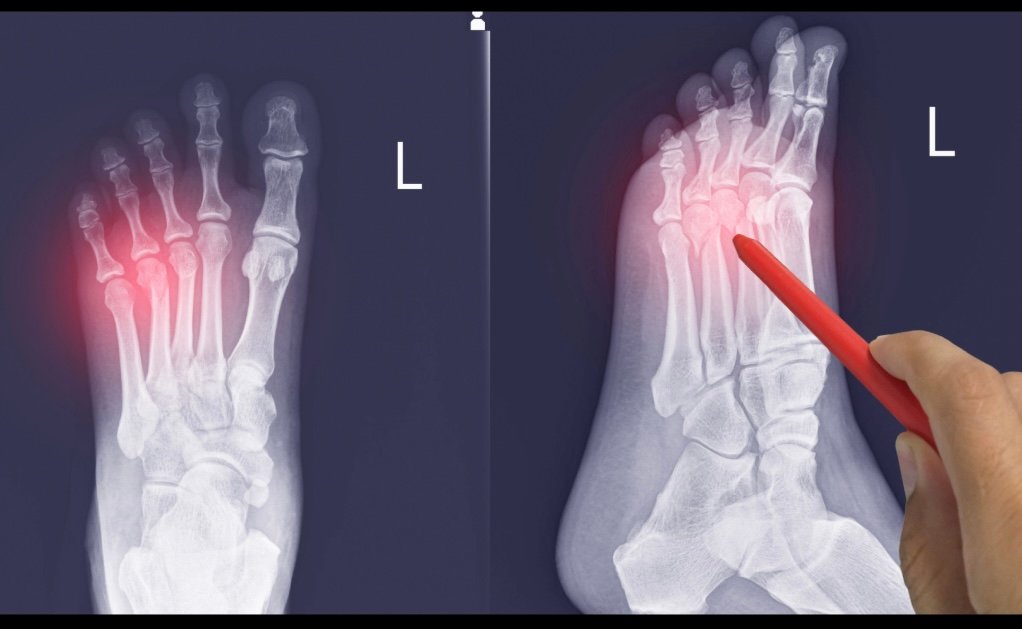

- Pruebas de imagen: radiografías, resonancia magnética o ecografía para detectar microfracturas.